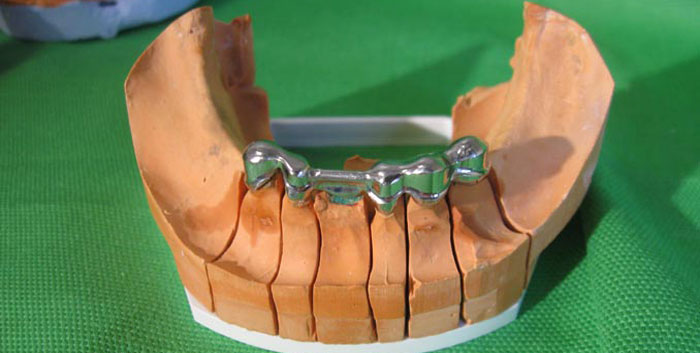

Diese Prothesenart wird auch „Teleskopprothese“ genannt. Die natürlichen Zähne werden angeschliffen, um das Metallgerüst aufnehmen zu können. Das Gerüst wird fest auf den angeschliffenen Zähnen befestigt. Mittig am Gerüst befindet sich ein Steg, auf welchem ein Präzisionsaufsatz befestigt wird.

Der innere Teil der Stegprothese, welcher am Zahnfleisch anliegt, wird mit einem Metallgerüst und einer Präzisionsverbindung gefertigt (das gelbe Teil im Metallgerüst).